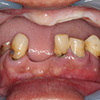

6.维护,保养

义齿种植治疗完成之后,为了义齿能够更长时间使用,必须进行家庭维护与定期的检查。 在医生的指导下,正确的清洁牙齿。另外,半年一次到医院定期检查。